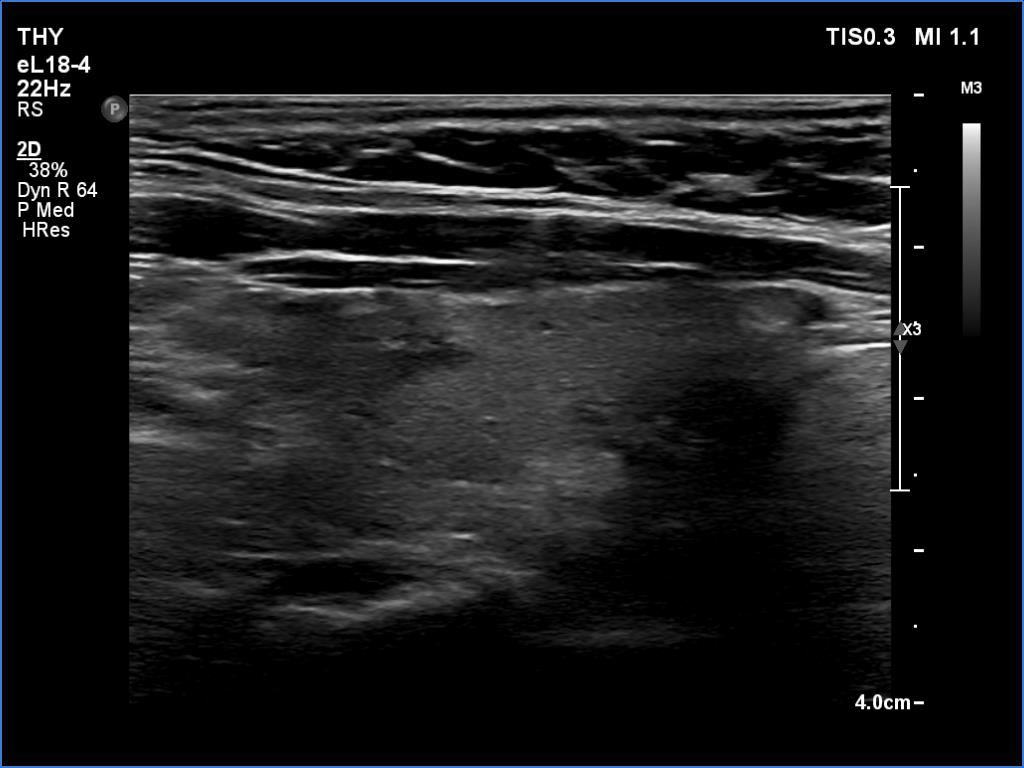

Elastography - case 188 (ultrasonographic picture 3)

Right lobe, longitudinal scan - set to higher level of harmonization. There is an irregularly shaped hypoechoic area in the upper part of the lobe.